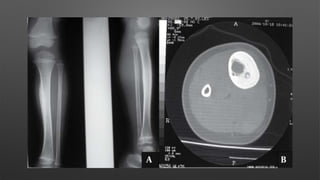

Aneurysmal Bone Cyst

• A benign and non-neoplastic reactive bone lesion filled with multiple blood-filled cavities

• can be locally destructive to normal bone and may extend to soft tissue

• Epidemiology - 75% of patients are < 20 yrs.

• Location

• 25% in spine

• 20% in long bones (distal femur, proximal tibia)

• usually in metaphysis

• metatarsal is the most common location in the foot

• posterior elements of pelvis

• Imaging

• Radiographs

• expansile, eccentric and lytic lesion with bony

septae ("bubbly appearance")

• usually in metaphyseal

• classic cases have thin rim of periosteal new

bone surrounding lesion

• no matrix mineralization

• MRI or CT scan

• will show multiple fluid lines

• lesion can expand into soft tissue